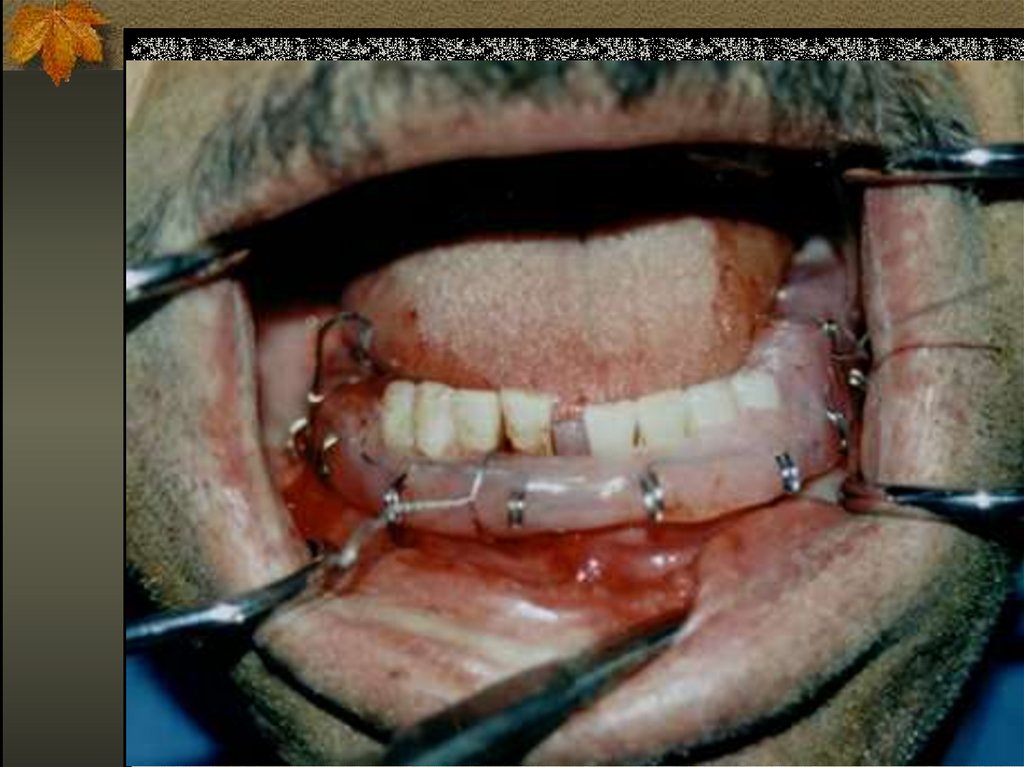

11. Vestibüler arklar (şineler)(ateller)

Ateller, fragmanları ve çeneleri aynı

anda birbirine birleştirmek maksadıyla

uygulanır. Aparey diş kavsinin

uzunluğunca devam eder devamlılık

lingual ve vestibül yüzdede aynıdır.

Ateller dişlere ligatürler vidalar veya

bilezikler yardımıyla bağlanır.